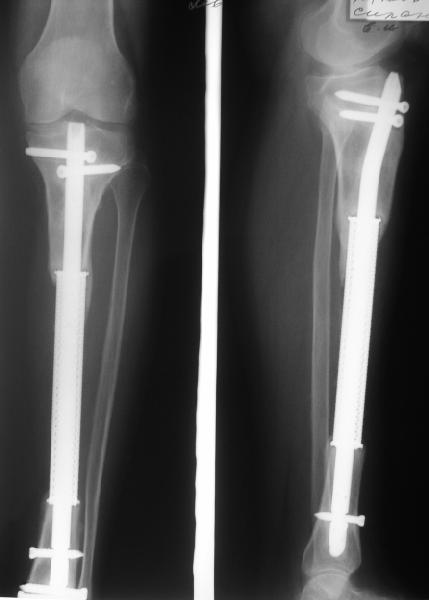

В приложении рентгенограмма через год после операции.

Сколько лет прослужит кейдж со штифтом? Ведь это металл и подвержен усталостным деформациям. Возможно проблемы начнуться раньше. Например на верхней границе контакта кейджа и кости уже сейчас можно отметить резорбцию. Или проблемы решатся по мере поступления и какие на Ваш взгляд можно ожидать?